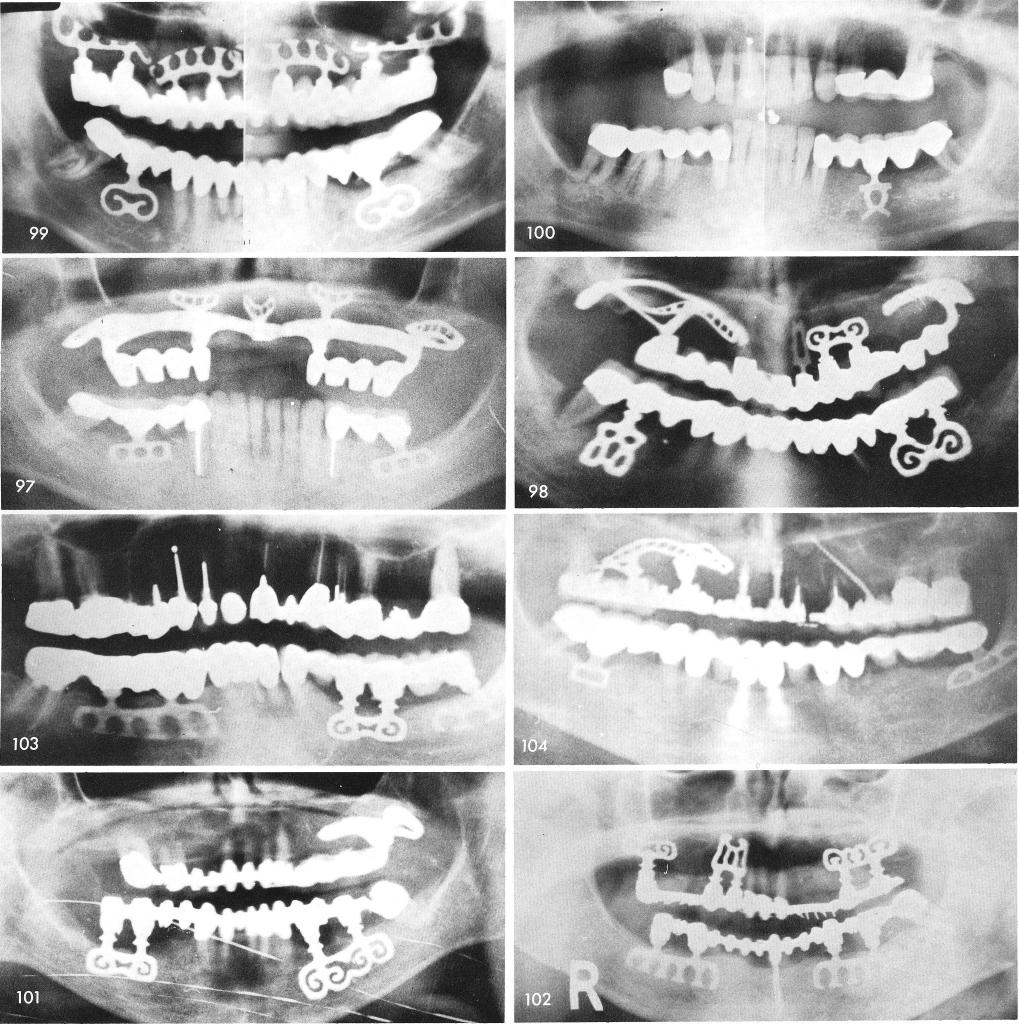

Mandibular Implants (published 1977)   Dr. Leonard I. Linkow